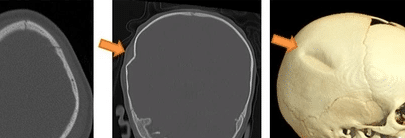

De aangesnelde arts (als wij als gespecialiseerd verpleegkundige aangeven dat wij NU een arts nodig hebben, wordt dat gelukkig zeer serieus genomen), wilde direct een CT-scan maken. In de CT-ruimte kwam ook de neuroloog (op de hoogte gebracht door de SEH arts), met ferme passen binnen, net toen de CT afgedraaid werd. De ruimte viel stil. We zagen meerdere breuken in de schedel van het kleine meisje en zowel bloedingshaarden als zwelling in de hersenen. De kans dat dit door een mogelijke val kwam, werd met de minuut kleiner. Moeder en vader bleven het gehele proces ook angstvallig op de achtergrond en liepen (achteraf gezien) absoluut niet over van ongerustheid. Wij echter wel.

Als de hersenen gaan zwellen, komen deze op een bepaald punt in de verdrukking – de schedel geeft niet mee. Wanneer de druk in de hersenen te hoog wordt, is het soms nodig de hersenen ruimte te kunnen geven om te kunnen opzwellen. Hierbij dient de schedel te worden geopend. Er wordt dan een ingreep verricht, waarbij een groot deel van de schedel wordt verwijderd. Dit ‘schedelluik’ wordt dan bewaard om later, in betere klinische conditie, terug te kunnen plaatsen.

Echter, de trekkingen in combinatie met de CT-scan lieten zien dat dit kindje al een enorme zwelling in de hersenen had zitten, waardoor deze al in de verdrukking waren gekomen. Als wij een vermoeden van kindermishandeling hebben of er is een onduidelijke oorzaak van de letsels, wordt het hele lichaam nagekeken op letsels.